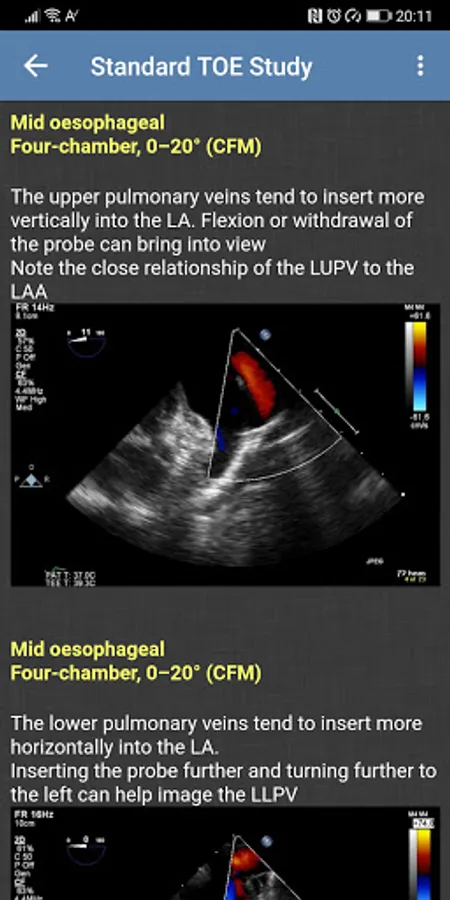

- Standard TOE Study